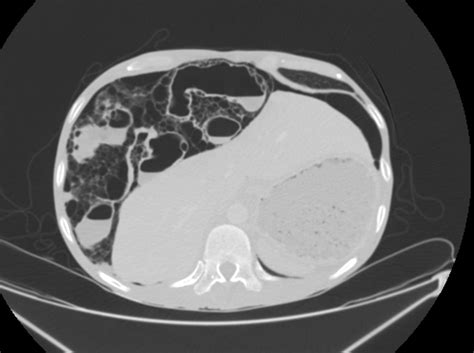

CT Scan The gold standard; provides detailed visualization of gas cysts.

When reviewing imaging, radiologists look for the specific appearance of "bubbly" gas collections along the serosal or submucosal surfaces. Differentiating these cysts from free air (pneumoperitoneum) is the most critical step for the radiologist to ensure the patient is not facing a surgical emergency.